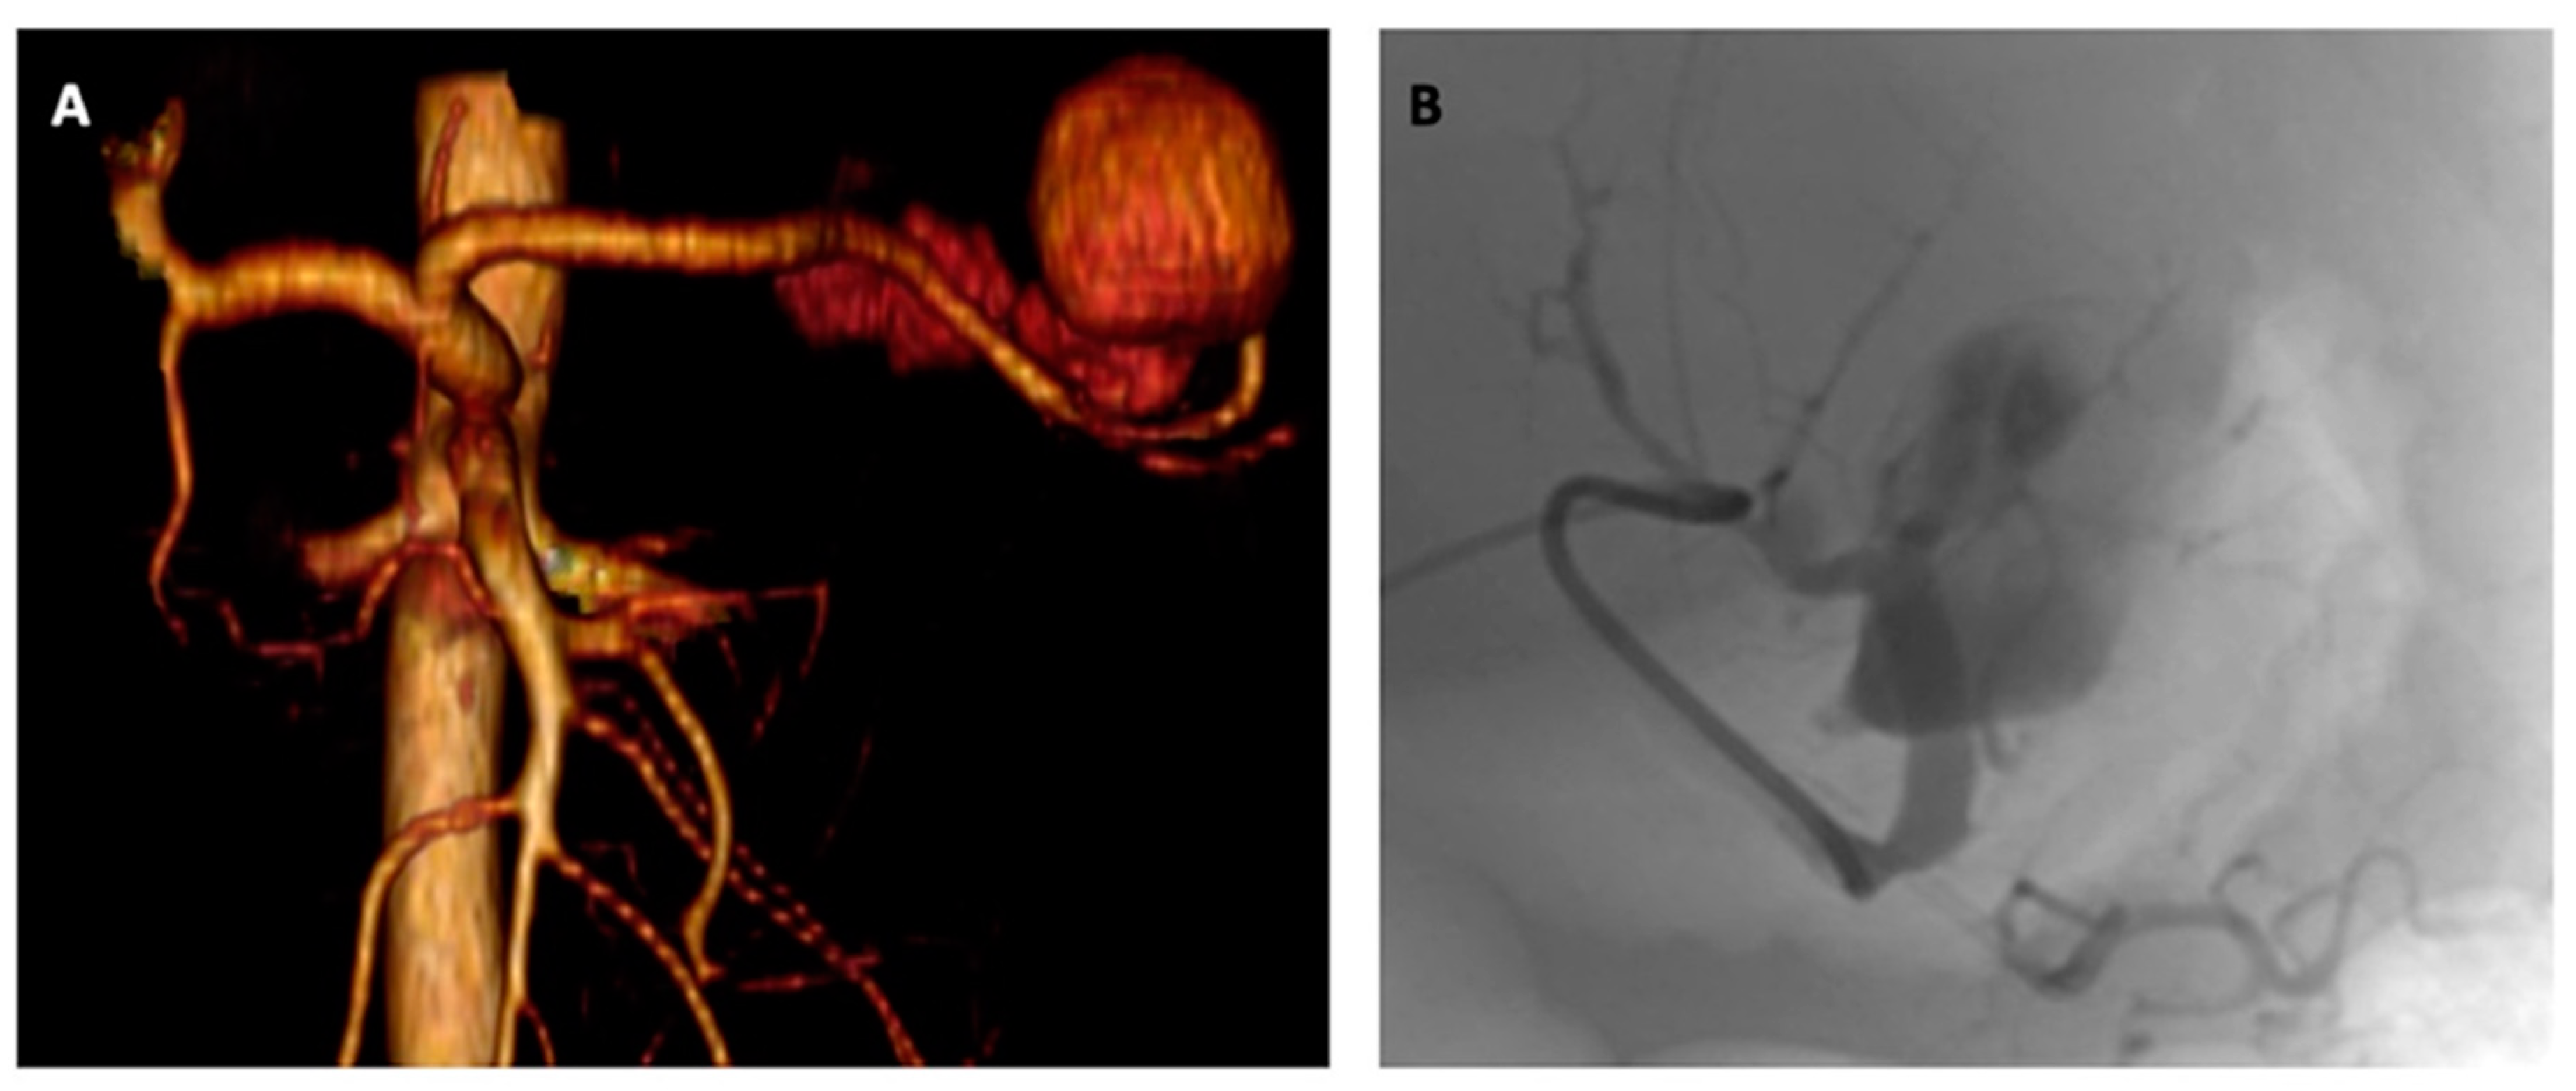

2. Detailed Case Description